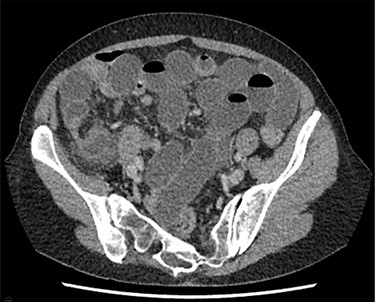

A 68-year-old woman presented to the surgical assessment unit with a 1-day history of colicky lower abdominal pain, distention and vomiting. She had a background of diverticular disease, and no previous abdominal surgery. On examination, her initial observations were normal, she was mildly dehydrated, tender over the right lower quadrant of her abdomen with mild abdominal distension. Admission blood tests showed leucocytosis (WBC 15.9), but the remainder was otherwise within normal limits. Initial differential diagnoses were appendicitis and diverticulitis. Contrast-enhanced CT of the abdomen and pelvis (Fig. 1) showed a small bowel obstruction, with multiple dilated small bowel loops in the pelvis and a transition point in the right iliac fossa. Initial management with NG tube, intravenous fluid and bowel rest was started. The patient underwent a diagnostic laparoscopy on the assumption that this could be a congenital band adhesion. Intraoperatively, a loop of terminal ileum was entrapped in the lateral paracaecal recess (Fig. 2). This recess was opened with laparoscopic scissors to release the entrapped segment. The released small bowel loop appeared viable on intraoperative assessment, so no resection was needed (Fig. 3). The recess was then opened completely along the ascending colon by dividing the lateral peritoneal reflection to prevent recurrence. Post-operatively, the patient recovered uneventfully, and she was discharged on day four.

CTAP showing multiple loops of dilated small bowel with transition point in the right iliac fossa.